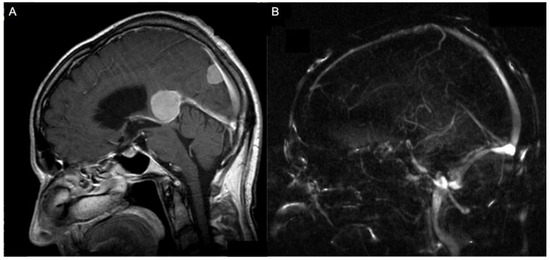

2.2. Volumetric Analysis, Vascular Features, and Tentorial Angle

| Infiltration of the straight sinus | 1 | |

| Infiltration of the superior sagittal sinus | 2 | |

| Displacement of the straight sinus | 5 | |

| Displacement of the vein of Galen | 4 | |